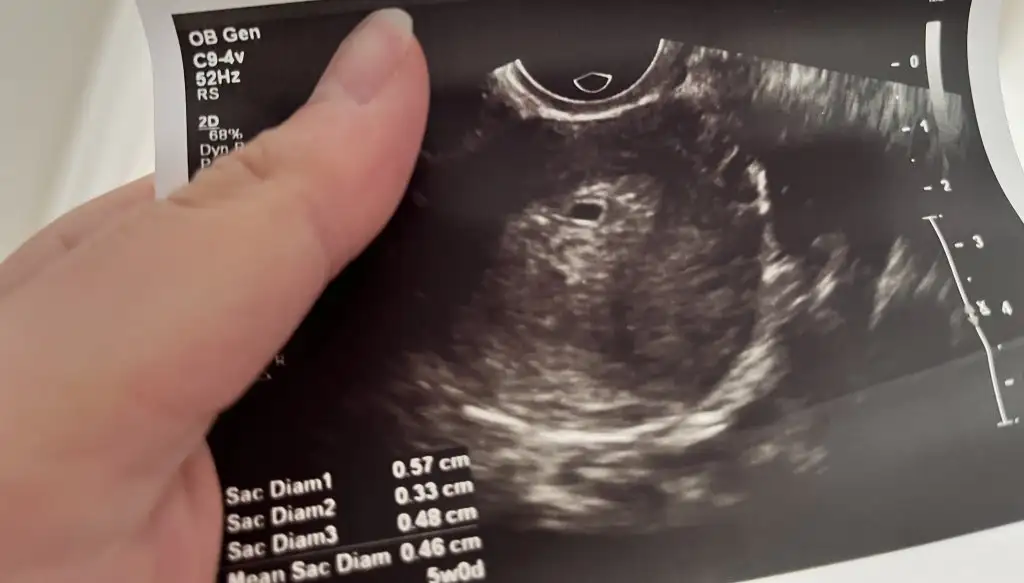

Özeldeki karından baktılar. E madem kese düzgünse niçin düşük dedi anlamadım. Ne zaman düşer bilemiyorum pazartesi tekrar gel dedi. Bide ağlıyorum milletin içinde rezil bir durum ya. Ben düşük yapıyorum diye gittim devlete. Vajinadan baktı ultrasonda kese düzgün dedi. Aslında özeldekinin raporundaki ultrasona bakıyorum orda da etrafı yuvarlak. Ben anlamadım. Dur buraya yükliyim belki anlayan çıkar 🥺

Bu da devletteki ultrason. Kanamam hala kırmızı pıhtısız adet gibi bu arada 😕 yani karışık bir durum gerçekten